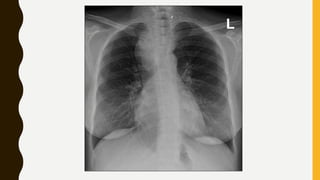

INVESTIGATIONS

• X-ray neck :AP & Lateral view

• CT scan : to look for retrosternal extension

INVESTIGATIONS • Thyroid functiontests • Ultrasonography (USG) • Fine needle aspiration cytology (FNAC) • Complete blood picture (CBP) • X-ray neck :AP & Lateral view • CT scan : to look for retrosternal extension • Thyroid scan-contains radioactive I • Indirect laryngoscopy : to see vocal cord mobility